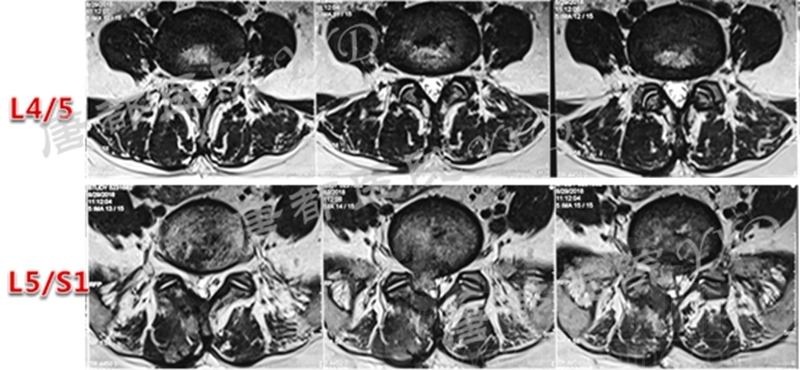

影像学检查:

诊断:腰椎间盘突出症术后复发

手术方案:显微镜辅助MI-TLIF腰椎翻修术